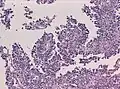

Менинготелиоматозная менингиома состоит из мозаикоподобно расположенных клеток с овальным или округлым ядром, которые содержат умеренное количество хроматина. Строма опухоли представлена немногочисленными сосудами и тонкими тяжами соединительной ткани, которые окаймляют клеточные поля. Характерны концентрические структуры из наслаивающихся одна на другую уплощённых опухолевых клеток. Центр новообразования часто обызвествлён[3].

Фиброзная менингиома состоит из фибробластоподобных клеток, которые располагаются параллельно друг другу и складываются в переплетающиеся между собой пучки, содержащие соединительнотканные волокна. Ядра вытянутые. Могут встречаться концентрические структуры и псаммомные тельца[3].

Переходная менингиома включает элементы менинготелиоматозной и фиброзной менингиом[3].

Псаммоматозная менингиома содержит большое количество псаммомных телец[3].

Ангиоматозная менингиома обильно васкуляризирована, содержит большое количество кровеносных сосудов[7].

Микрокистозная менингиома содержит большое количество микрокист, окружённых опухолевыми клетками звёздчатой формы[8].

Секреторная менингиома является редким гистологическим вариантом данного новообразования. Для неё характерна секреция веществ, которые формируют гиалиновые включения[9].

Менингиомы с обилием лимфоцитов по определению содержат большое количество включений лимфоцитарных масс.

Для метапластических менингиом характерна метаплазия (трансформирование) менинготелиальных клеток в клетки другого типа (к примеру, адипоциты)[10].

Менинготелиоматозная эпендимома

Фиброзная менингиома

Переходная менингиома

Ангиоматозная менингиома

Секреторная менингиома

Папиллярная менингиома

Анапластическая менингиома

Атипическая менингиома

Хордоидная менингиома

Микрокистозная менингиома